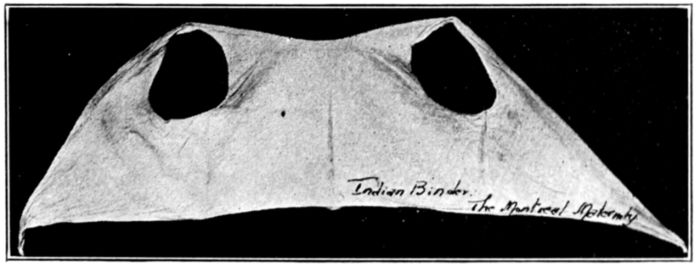

| 127. | Indian binder | 347 |